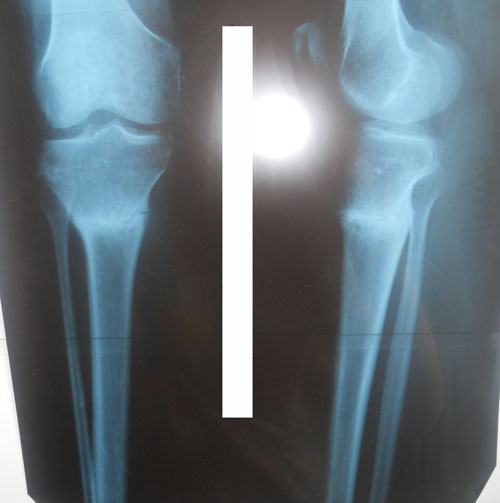

- Диагноз: Варусная деформация ног

Дата операции 05.12.2013г.

Исходник .